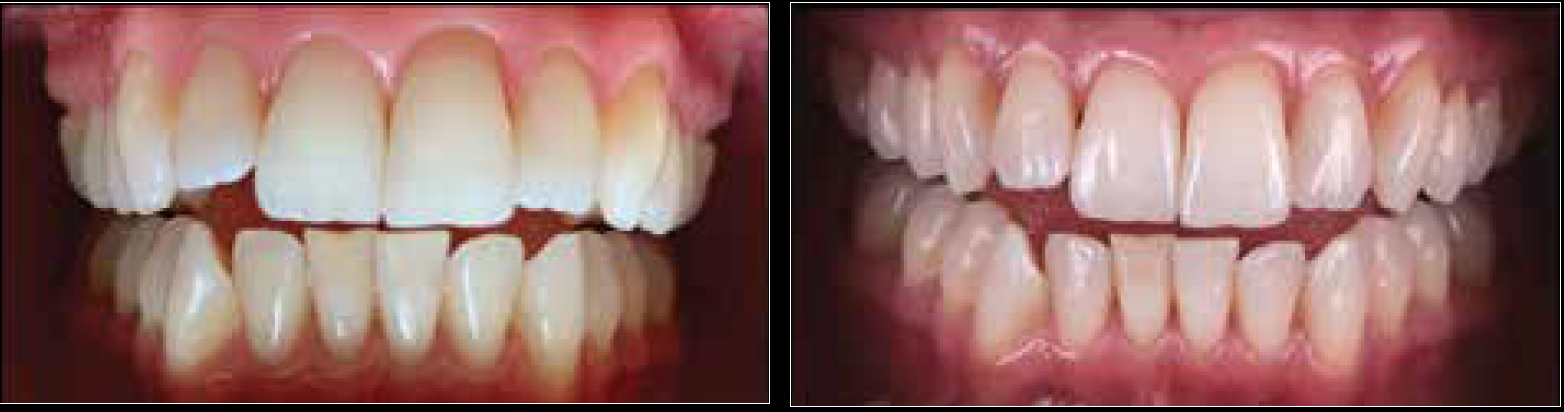

Fig 15. Smartphone dental photography can also be used in laboratory shade communication. In these images taken using MDP, the photo on the left shows value selection, while the one on the right shows chroma/hue selection.

Figure 15